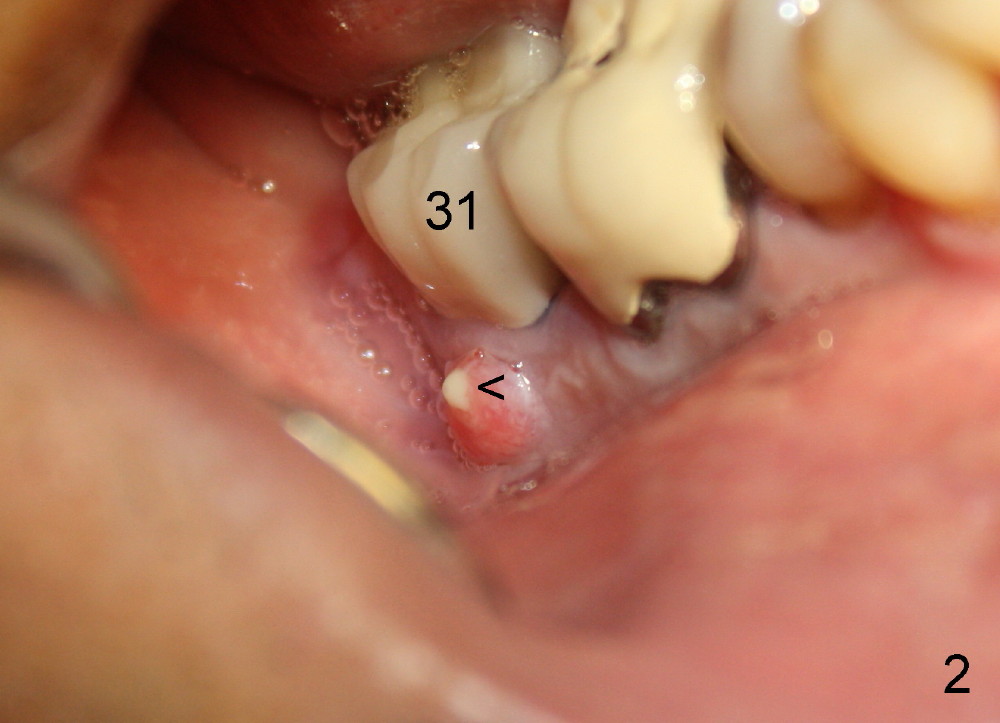

A 51-year-old man has experienced pain and swelling in the lower right 2nd molar for 7 months (Fig.1, P: post in the mesial root; <: gutta percha inserted into a buccal fistula). Fig.2 is taken immediately before extraction (<: purulent discharge from the mesiobuccal fistula) and immediate implant (Fig.3 implant design: 7x14 mm). A vertical root fracture is noted in the mesial root (Fig.4: lingual view). The septum is in fact absent, as compared to Fig.1. The mesiobuccal plate is low; the osteotomy starts lingual to the center of the socket. Fig.5 shows a 4.5x17 mm tap in place: approximately 3.5 mm in the new bone (~2.5 mm from the inferior alveolar canal). When a 7x17 mm tap (14 mm from the gingival margin) is placed in the socket, it looks relatively small. Fig.6 shows a 8x14 mm implant in place with a small gap distally. Mineralized cancellous allograft and Osteogen mixture is placed mainly buccally, followed by a thin strip of collagen dressing and sutures (Fig.7); an abutment (A) is placed to keep perio dressing in place. The perio dressing does not stay long. The buccal portion dislodges by itself 5 days postop. The lingual portion is removed in clinic. New dressing is going to be re-applied, because the buccal wound has not completely healed (Fig.8 <, albeit asymptomatic) with partial exposure of the bone graft (*). Why is the dressing lost so early? The abutment is not long enough; there is plenty of occlusal clearance (Fig.9 arrows). A longer abutment is used to increase mechanical retention for perio dressing (Fig.10). By the time the second perio dressing dislodges, the wound has healed (Fig.11, 13 days postop).